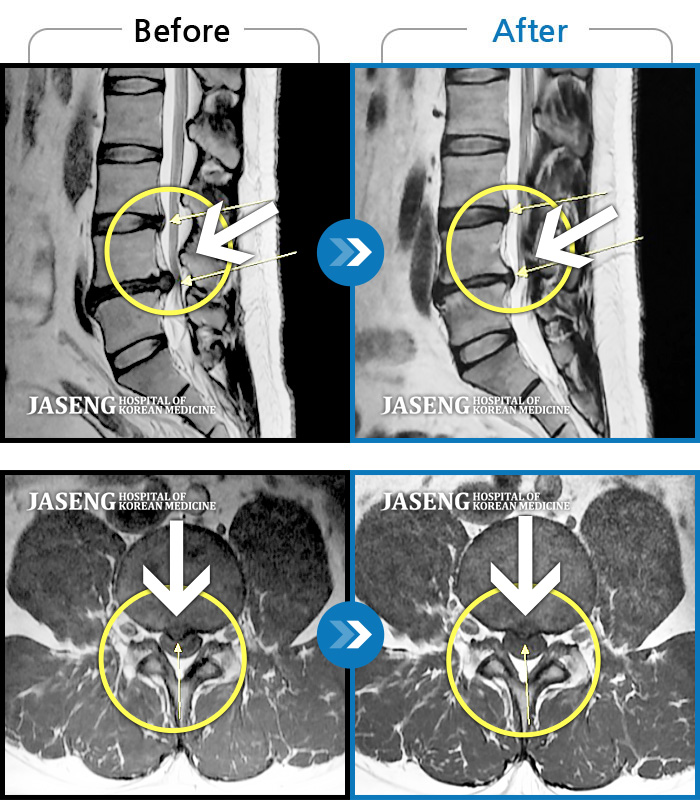

MRI 치료사례

요통 및 우측 골반 통증, 우측 대퇴부 외측 통증